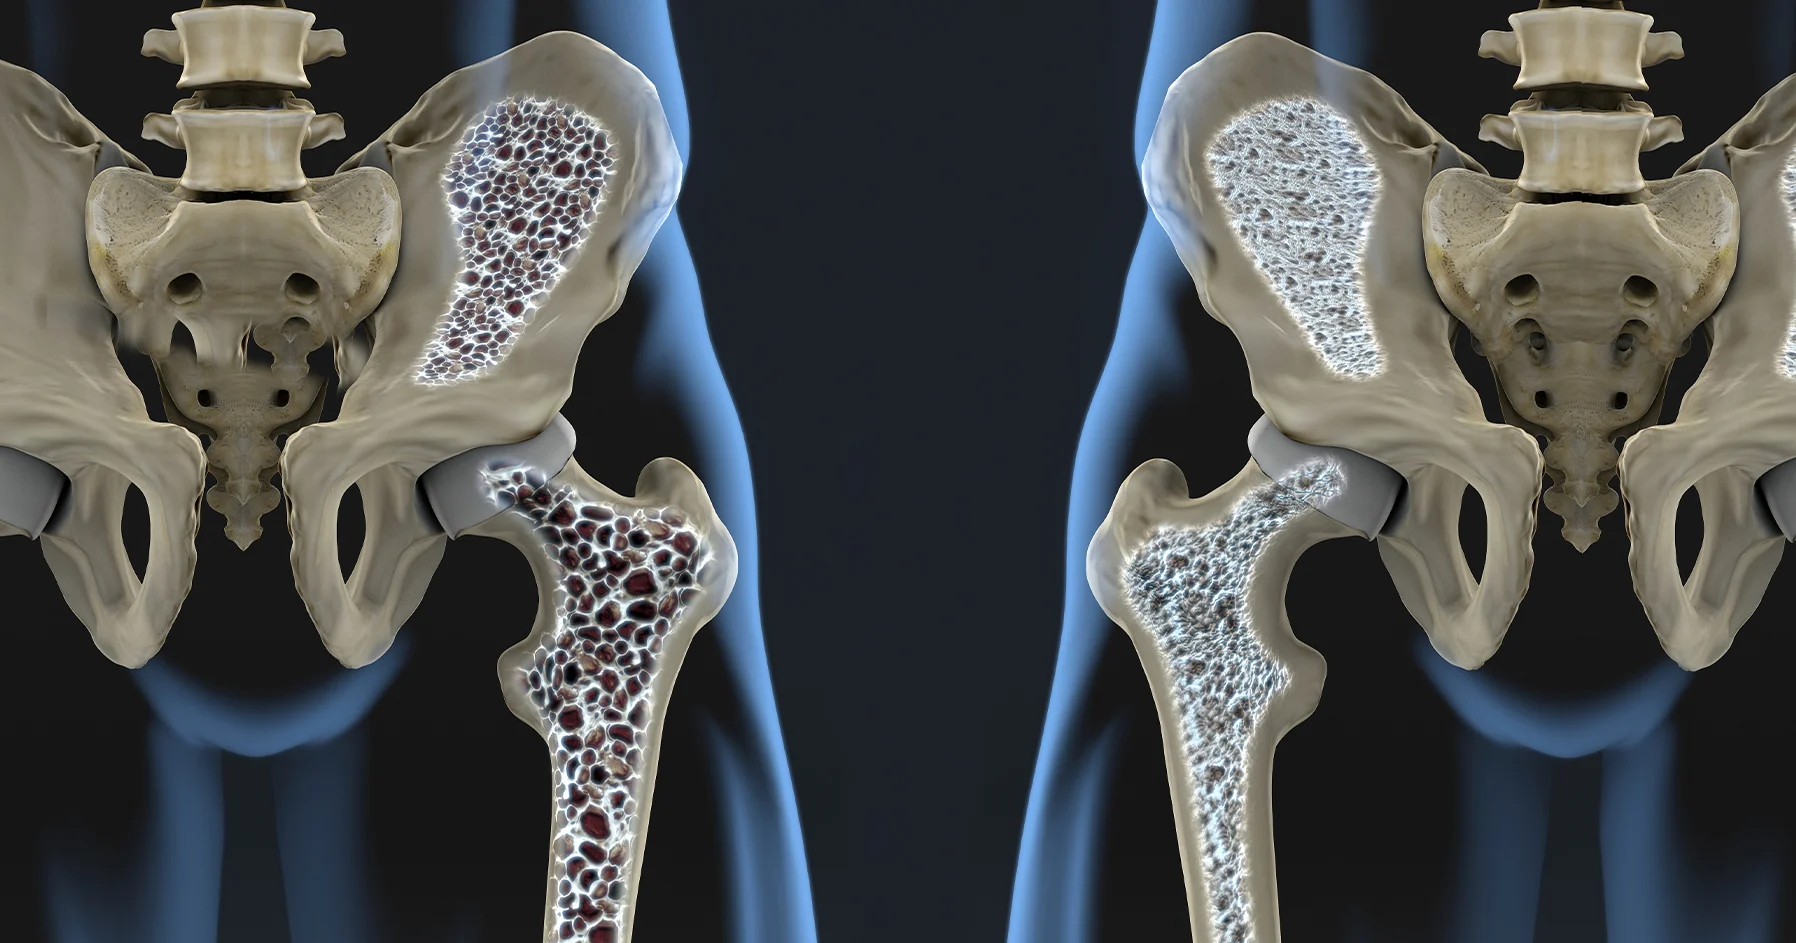

Ποια είναι τα πρώτα σημάδια της οστεοπόρωσης;

Στον σύγχρονο δυτικό κόσμο τα τελευταία 50 χρόνια το προσδόκιμο επιβίωσης (life expectancy) έχει ανέβει κατά 15 χρόνια τουλάχιστον. Η έκθεση του πληθυσμού σε μεγαλύτερη διάρκεια ζωής σε συνδυασμό με υποβάθμιση  της ποιότητας διατροφής και την ελάττωση της σωματικής δραστηριότητας οδηγούν σε σημαντική αύξηση της επίπτωσης της οστεοπόρωσης. Ο ορισμός της οστεοπόρωσης είναι ο εξής. Οστεοπόρωση είναι η κατάσταση κατά την οποία παρατηρείται  σημαντική επιβάρυνση των οστών και το αποτέλεσμα αυτής  είναι τα κατάγματα των οστών.  Σύμφωνα με τα πρόσφατα στοιχεία μία στις τρείς γυναίκες και ένας στους τέσσερεις άνδρες θα υποστούν ένα κάταγμα οστεοπόρωσης. Κατάγματα οστεοπόρωσης θεωρούνται όλα τα κατάγματα χαμηλής βίας δηλαδή τα κατάγματα που προκαλούνται από μια πτώση ή και σε πολλές περιπτώσεις χωρίς καμία προφανή αιτία.  Τα κατάγματα που προκύπτουν από τροχαία ατυχήματα από έντονες αθλητικές δραστηριότητες ή από πτώση από ύψος δεν θεωρούνται κατάγματα οστεοπόρωσης. Τα πιο συνηθισμένα κατάγματα οστεοπόρωσης είναι τα κατάγματα σπονδυλικής στήλης που οδηγούν σε μείωση του ύψους  κύφωση και απώλεια ισορροπίας τα κατάγματα ισχίου ή γοφού όπως λέγονται τα οποία έχουν υποχρεωτική ανάγκη άμεσης χειρουργικής επέμβασης και προκαλούν τεράστια επιβάρυνση στην συνολική υγεία του πάσχοντος και τέλος κατάγματα καρπού και ποδοκνημικής άρθρωσης. Η αντιμετώπιση των οστεοπορωτικών καταγμάτων πρέπει να γίνεται από εξειδικευμένη ιατρική ομάδα γιατί η θεραπευτική αντιμετώπιση δεν πρέπει να σταματάει στην χειρουργική αποκατάσταση καθώς η αντιμετώπιση του αιτίου του κατάγματος που είναι η οστεοπόρωση η θεραπεία είναι απολύτως επιβεβλημένη και επείγουσα. Τα πρώτα σημάδια της οστεοπόρωσης είναι επιδείνωση της στάσης του σώματος  μείωση του ύψους, μείωση της φυσικής δύναμης και αντοχής, παρουσία πόνου στην πλάτης και στην λεκάνη και τέλος ανεξήγητα κατάγματα. Η αλήθεια είναι ότι πρέπει να προλαμβάνουμε την οστεοπόρωση γιατί όταν εμφανίζονται τα συμπτώματα είναι ήδη αργά. Αυτό είναι ακόμα πιο σημαντικό στους άνδρες στους οποίους η οστεοπόρωση  ξεκινάει 15 χρόνια περίπου μετά από τις γυναίκες αλλά η βαρύτητα των καταγμάτων είναι πολύ μεγάλη και επίσης ο ανδρικός πληθυσμός συνήθως δεν είναι καθόλου ευαισθητοποιημένος για την επίπτωση και την σοβαρότητα των αποτελεσμάτων της οστεοπόρωσης.  Για την πρόληψη της εμφάνισης της οστεοπόρωσης και των σοβαρότατων συνεπειών της πρέπει να υπάρχει έλεγχος οστικής πυκνότητας στις γυναίκες μετά την εμμηνόπαυση για να υπάρχει ένα σημείο αναφοράς και σύγκρισης με μελλοντικές εξετάσεις.  Η μέτρηση της οστικής πυκνότητας γίνεται σε δύο σημεία.  Πρώτον στην οσφυϊκή μοίρα της σπονδυλικής στήλης όπως λέγεται στην μέση και δεύτερον στο άνω άκρο του μηριαίου ή όπως λέγεται στο ισχίο. Η αξία της μέτρηση στην οσφυϊκή μοίρα της σπονδυλικής στήλης είναι μεγαλύτερη στις νεότερες γυναίκες δηλαδή ηλικία έως 70 ετών ενώ η μέτρηση της οστικής πυκνότητας του ισχίου έχει μεγαλύτερη αξία για γυναίκες μεγαλύτερης ηλικίας καθώς η μέτρηση αυτή σχετίζεται καλύτερα με την πιθανότητα κατάγματος ισχίου.  Για τους άνδρες είναι σημαντικό να γίνεται μέτρηση μετά την ηλικία των 65 καθώς είναι χρήσιμο να χρησιμοποιηθεί για σύγκριση με μελλοντικές εξετάσεις.   Πέρα από τις εξετάσεις μέτρησης οστικής πυκνότητας ακόμα πιο σημαντική είναι η μέτρηση σημαντικών παραγόντων του οστικού μεταβολισμού σε εξετάσεις αίματος όπως είναι το ασβέστιο ο φώσφορος η βιταμίνη D η παραθορμόνη η αλκαλική φωσφατάση και άλλοι δείκτες οστικού μετααβολισμού. Η συνεισφορά του οικογενειακού ιατρού ή του γενικού ιατρού ή του παθολόγου στην ενημέρωση αλλά και στην παρατήρηση κάποιων συμπτωμάτων είναι εξαιρετικής σημασίας.  Πέρα από την προτροπή για έλεγχο στις προαναφερθείσες ηλικιακές ομάδες όλοι οι ασθενείς οποιασδήποτε ηλικίας που έχουν ανεξήγητα κατάγματα  οι ασθενείς που λαμβάνουν φάρμακα που επηρεάζουν τα οστά όπως η κορτιζόνη και οι ασθενείς που πάσχουν από συστηματικά νοσήματα που επιβαρύνουν τα οστά όπως για παράδειγμα η ρευματοειδής αρθρίτιδα ή η ελκώδης κολίτιτδα πρέπει να κάνουν πλήρη έλεγχο και να λαμβάνουν θεραπεία.